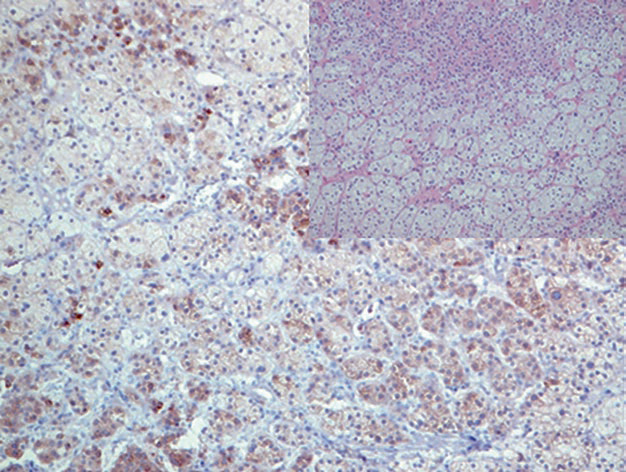

Figure 2. Adrenal cortical adenoma, inhibin positive in the cytoplasm.